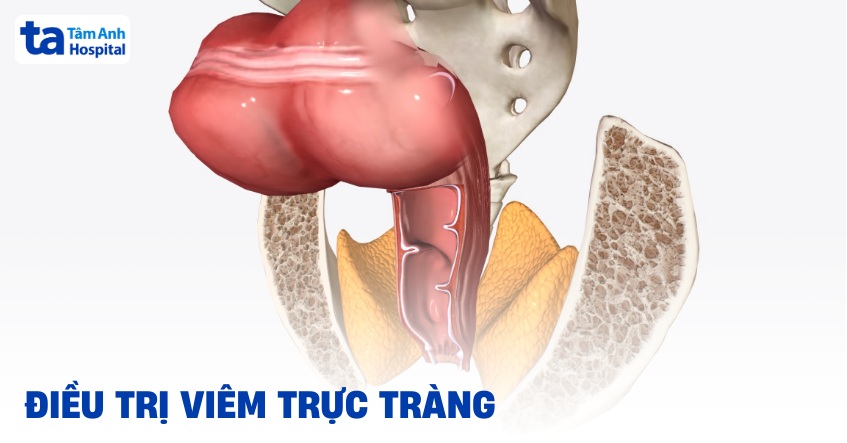

Trực tràng là một ống cơ nối với phần cuối của đại tràng. Phân khi đi ra khỏi cơ thể, phải di chuyển qua trực tràng. Viêm trực tràng là tình trạng niêm mạc trực tràng bị viêm, có thể gây đau trực tràng, chảy máu, tiết dịch, tiêu chảy và muốn đi đại tiện thường xuyên. Các triệu chứng bệnh có thể xảy ra và biến mất trong thời gian ngắn (cấp tính) hoặc diễn tiến thành mạn tính.